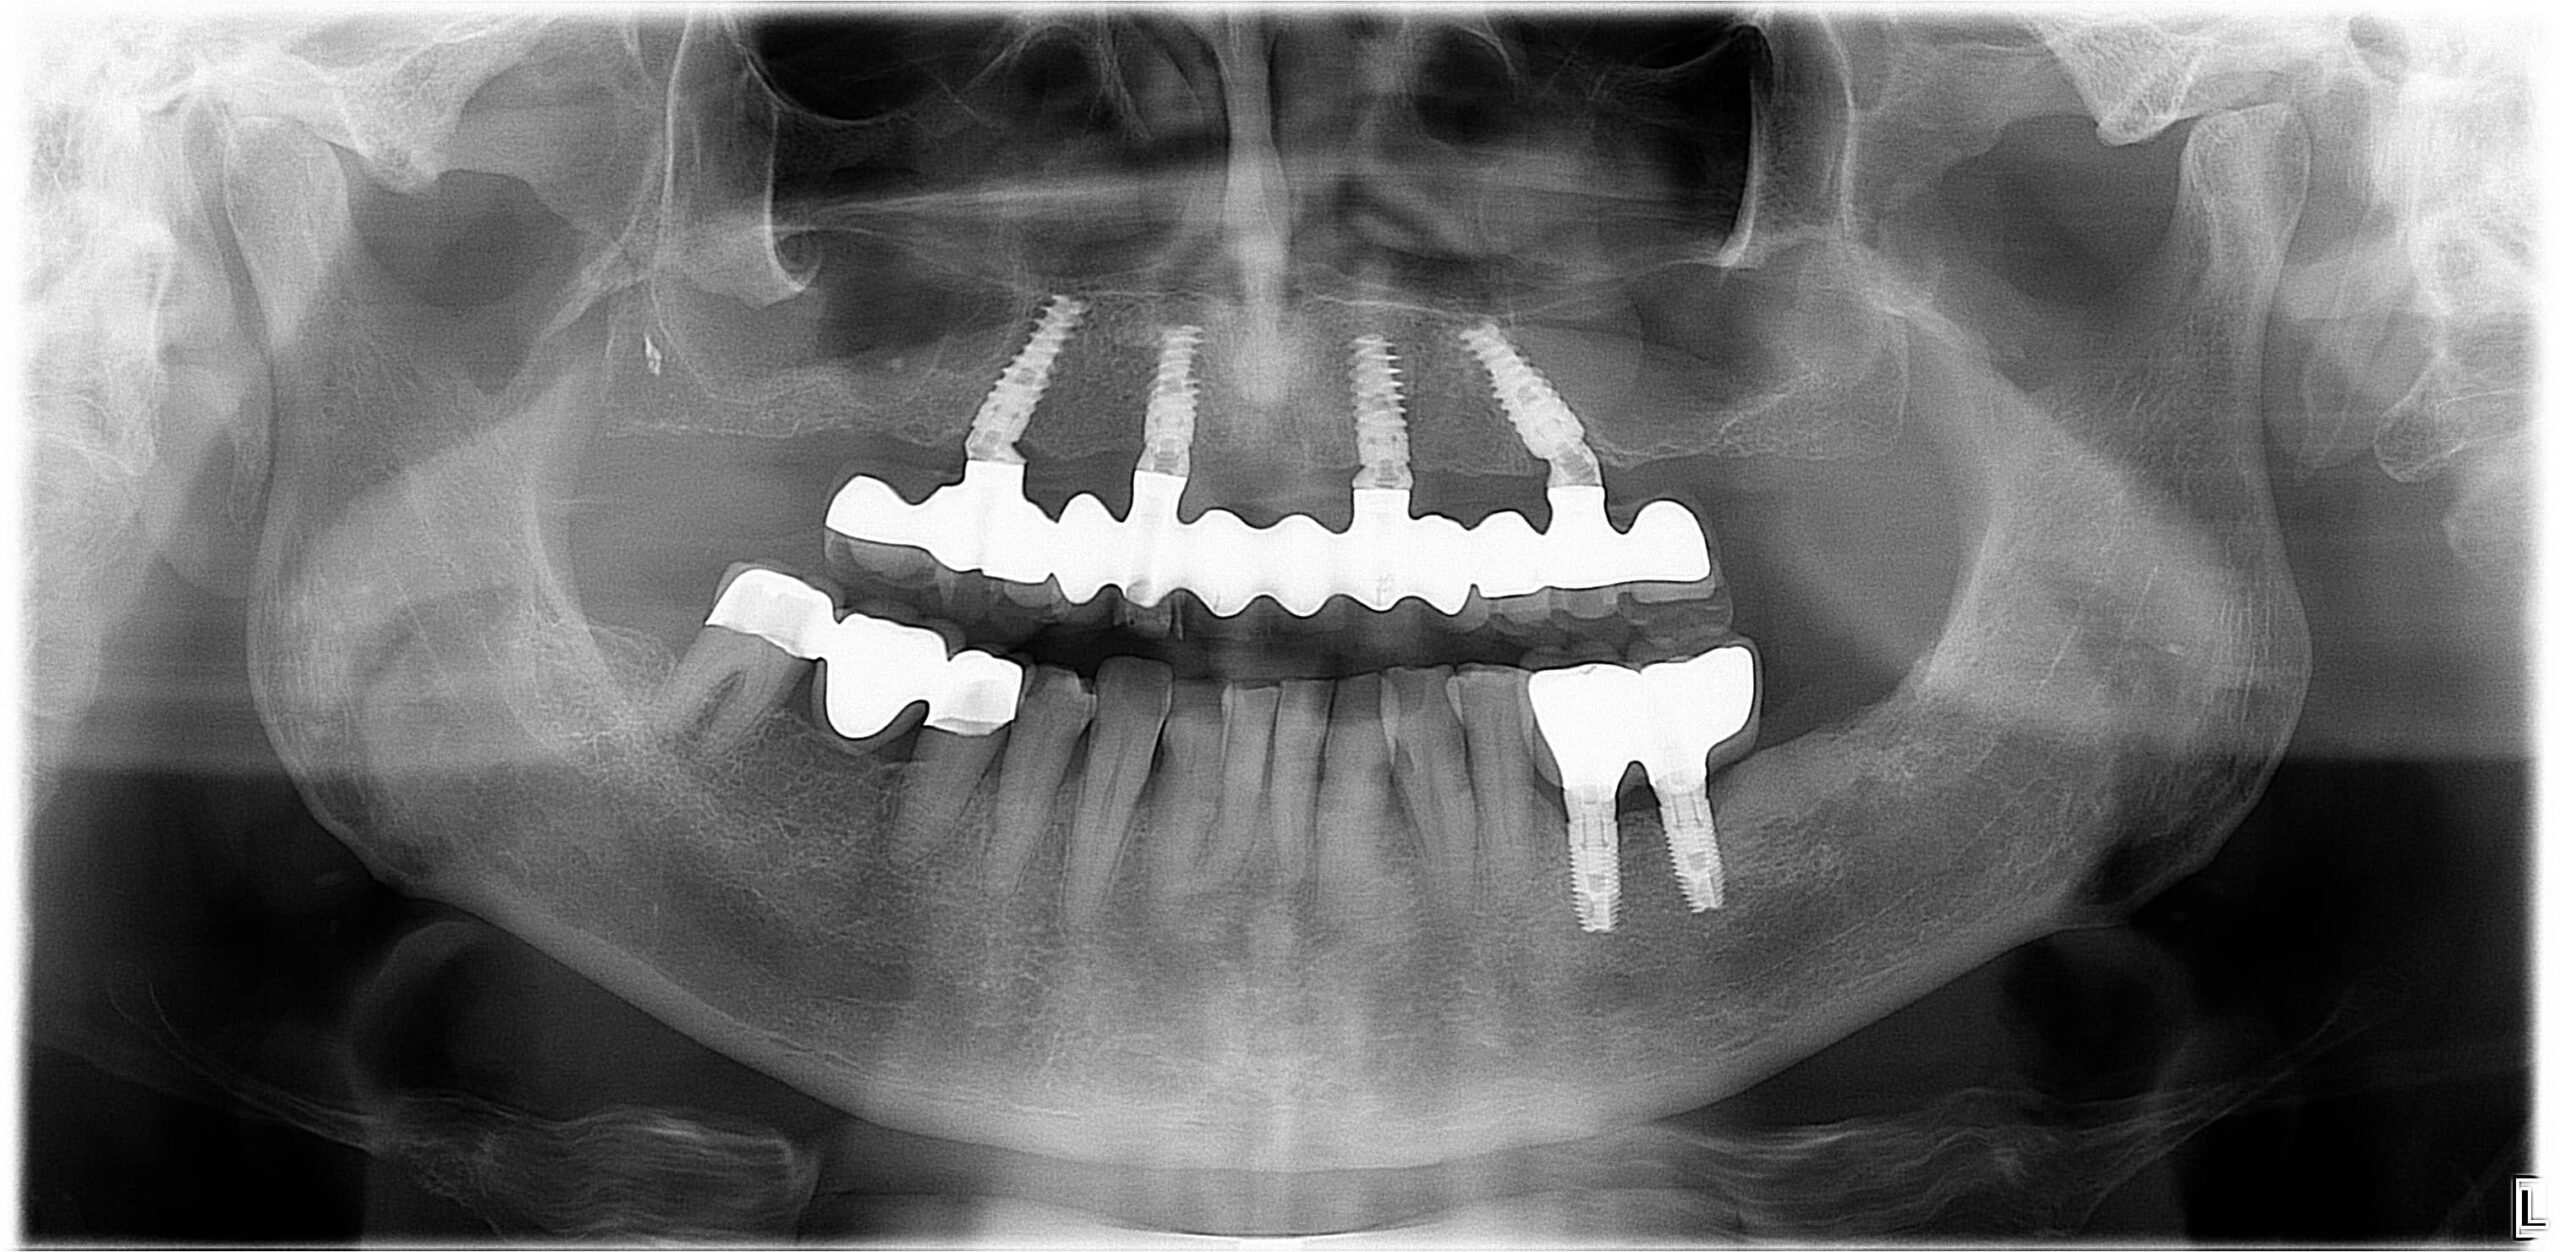

All-On-6 - Teljes rehabilitáció csavarozható, fix fogsorral, implantátummal

Az All-on-6 fogpótlás évek óta fennálló teljes foghiány esetén is ideális megoldás lehet, még akkor is, ha a csontvesztés előrehaladott állapotban van. Ezzel az innovatív fogászati megoldással visszaállítható a teljes rágóképesség, mintha csak saját fogait kapná vissza, és örökre elfelejtheti a kivehető fogsorát.

A csavarozható rögzítésnek köszönhetően a fosgsor és az implantátum kapcsolata bontható, így biztosítva a hosszú távú javíthatóságot.